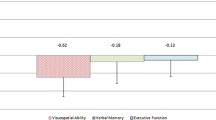

Groups comparisons

The two groups differed (p < 0.01, t test) for scores in ToL PEG and ToL CPU (when expressed in percent of maximum score the performances at PEG and CPU where very similar intra group, Fig. 3 Upper left and right). The difference was confirmed by the ANCOVA model (PEG, genotype p = 0.001 adjusted r 2 = 0.41; CPU, genotype p = 0.01 adjusted r 2 = 0.41).

We did not find any significant correlation with SPM8 for ICARS, CAG repeats and duration of the disease. We found a striking correlation with the two version of ToL (Fig. 3, Supplementary Fig. 14, 15, 16; Table 4, Supplementary Table 6). The ToL PEG correlated with a prevalently (83%) Anterior Cerebellum area of about 20,000 voxels with global maxima in x, y, z = 31, −33, −27 (Right Lobule IV–V near the boundary with Lobule VI). The clusters extended more in the Right Cerebellum (68%) and included many voxels in Lobules III–VI with small parts of the Right Parahippocampal Gyrus, Crus 1, 2 and Midbrain (Supplementary Table 6). The ToL CPU correlated with areas prevalently centred on the Posterior Cerebellum (71%) of about 25,000 voxels with global maxima in x, y, z = 38, −76, −36 (Right Crus 1 near the boundary with Crus 2). The clusters extended more in the Right Cerebellum (78%) and included Lobules III–VI, Crus 1, 2, VIII, Vermis I–V, Right Hippocampus and Parahippocampal Gyrus with small parts of Midbrain, Left Hippocampus and Parahippocampal Gyrus (Supplementary Table 6).

Correlation between Tower of London scores and atrophy patterns. Upper left Traditional Tower of London scores (ToL PEG) for controls (in blue, left histogram) and SCA2 (in green, right histogram), upper right Computerised Tower of London scores (ToL CPU) for controls (in blue, left histogram) and SCA2 (in green, right histogram). Error bars stand for SEM, *p < 0.05 two independent samples t test, ordinates units are in percent of maximum score. Lower left voxels volume correlated with ToL PEG, blue cross on the global maxima x, y, z = 31, −33, −27 mm; Lower right voxels volume correlated with ToL CPU, blue cross on the global maxima x, y, z = 38, −76, −36 mm. For all the contrasts the threshold was p < 0.001 uncorrected

We observed a correlation between Anterior Cerebellum and ToL PEG performance and between Posterior Cerebellum and ToL CPU. The main differences of the two tasks were that in the CPU version the sensorimotor feedbacks and skills, needed for fine coordination, were absent and on the contrary the Working Memory load was increased.

Tower of London planning task increases blood flow activity, as attested consistently by many PET and fMRI studies (e.g. Beauchamp et al. 2003; Boghi et al. 2006; Schall et al. 2003), in a network mainly composed by bilateral dorsolateral prefrontal, inferior parietal cortex and Cerebellum. These evidences converge with other theoretical, anatomical, physiological, clinical, and functional considerations that led to the incorporation of the cerebellum into the distributed neural circuits subserving cognition and emotion (Schmahmann 2010). In a recent meta-analysis (Stoodley and Schmahmann 2009), confirmed by a multiple fMRI tasks intra-subjects study (Stoodley et al. 2010), sensorimotor tasks activated the anterior Lobule IV–V and the adjacent Lobule VI. The posterior lobe was involved in higher-level tasks: executive functions activated the Lobules VI, Crus I and VIIb. These are the same areas that we observed as associated to different dysfunctions in the SCA2 patients. The dissociation between the coordinative and executive impairment was reported, regard prominence and evolution, in SCA2 patients (Le Pira et al. 2007). We hypothesise that this dissociation is linked to different areas of atrophy in the Cerebellum and that it resemble the dissociation founded in patients with cerebellar damage in different cerebellar areas (Stoodley and Schmahmann 2010). In both ToL tasks, we observed an association of the Right Cerebellum atrophy with the performances. This result is in agreement with the hand dominance of subjects and with the involvement of the frontal left cortex in these tasks that, with Right Cerebellum is active during planning. The role of cerebellum in Working Memory is well recognised and in the recent meta-analysis (Stoodley and Schmahmann 2009) authors highlighted, as well as for executive functions, the strongest activation in the lobule VI/Crus I in both hemispheres, during verbal Working Memory tasks. The increased Working Memory load in the ToL CPU respect to the classical version, may have played a role in finding the correlation between the posterior cerebellum and the ToL CPU.

The correlations of different versions of the test suggested a dissociation between dysfunctions in SCA2: the Posterior Cerebellum linked to the executive dysfunction and Working Memory and the Anterior Cerebellum linked to the coordinative dysfunction. Our results could also have a clinical relevance, supporting the fact that neuropsychological classical tests, when require motor coordination, may not be adequate for the assessment of patients with movement disorders.